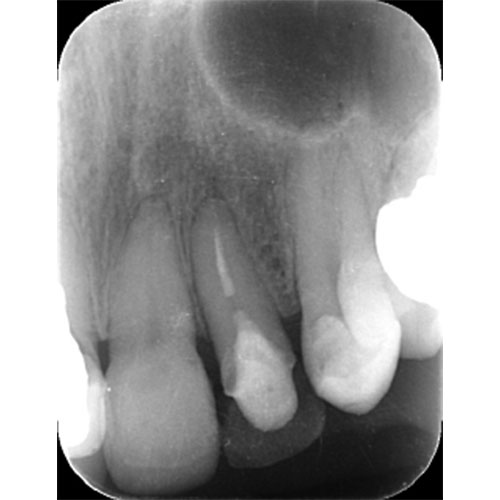

レントゲンで見ても、右上2では歯質が歯肉縁上にのこっていない。しかし歯根は長いのでMTMの適応症例です。

| 治療前で歯根が長いのがわかります。歯根がある程度長く無いと、MTMは行えません。 | MTM終了時のもの。フックが上の金属に接している。また根尖に透過像があるが、歯が動いた証拠です。 |